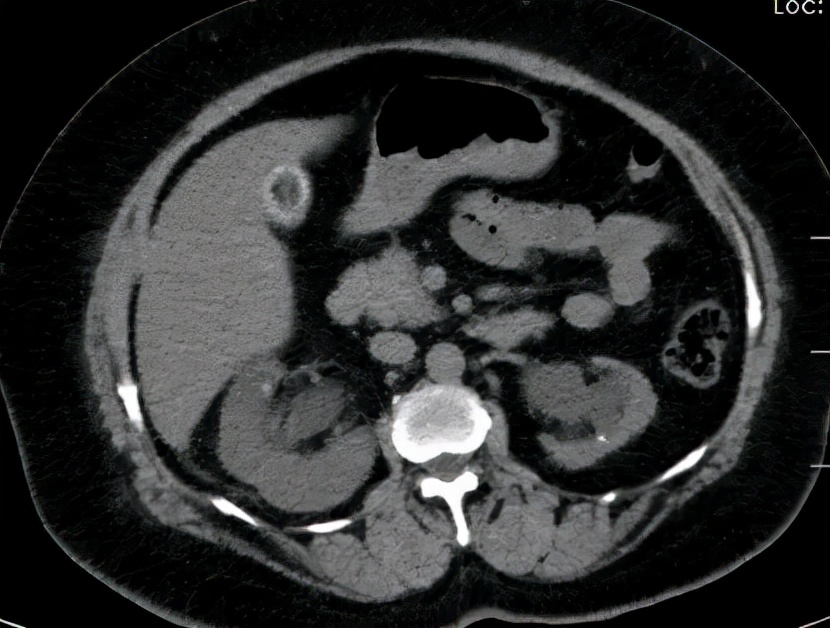

王卫国看了她的肾CT片子后解释说

你的左肾有结石、左输尿管也有结石

左肾明显萎缩表现,但仍有保留价值

原来是王大妈的右肾结石掉了出来

形成右输尿管结石合并肾积脓,尿源性脓毒症

再加上王大妈左肾有结石且明显萎缩

双肾梗阻,同时发生了急性肾功能不全